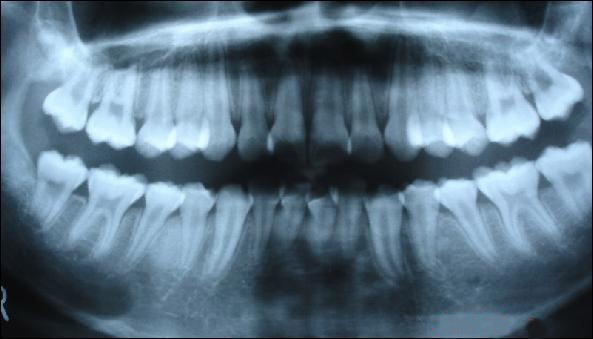

從上圖可以看出,牙槽骨被吸收,牙齦萎縮,牙縫變大

由此可見,如果我們不及時清洗牙結(jié)石,我們的牙齦就會反復充血發(fā)炎,形成慢性牙周病。久而久之,我們的牙槽骨一點一點地被吸收掉,牙就這樣一顆一顆地掉了。我們很多人以為,牙掉了沒關系,安上假牙不就完了嗎,現(xiàn)在還有種牙的,但是,我在看牙醫(yī)時,醫(yī)生告訴我,一定盡全力挽救每一顆牙,畢竟,所有安上去的牙,都不如原裝的好用。